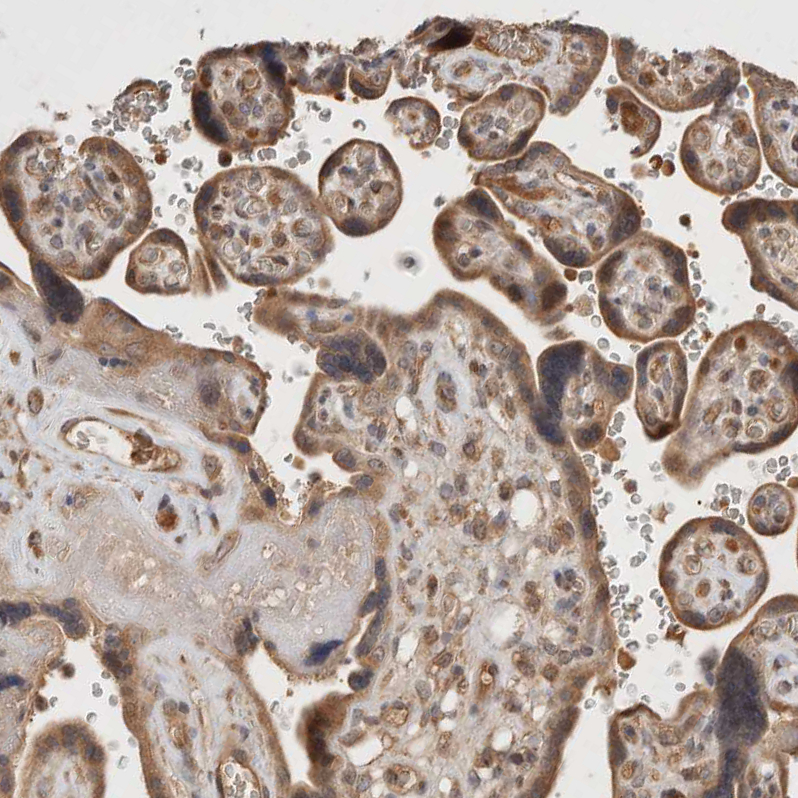

Immunohistochemical staining of human testis shows moderate cytoplasmic positivity in cells in seminiferous ducts.